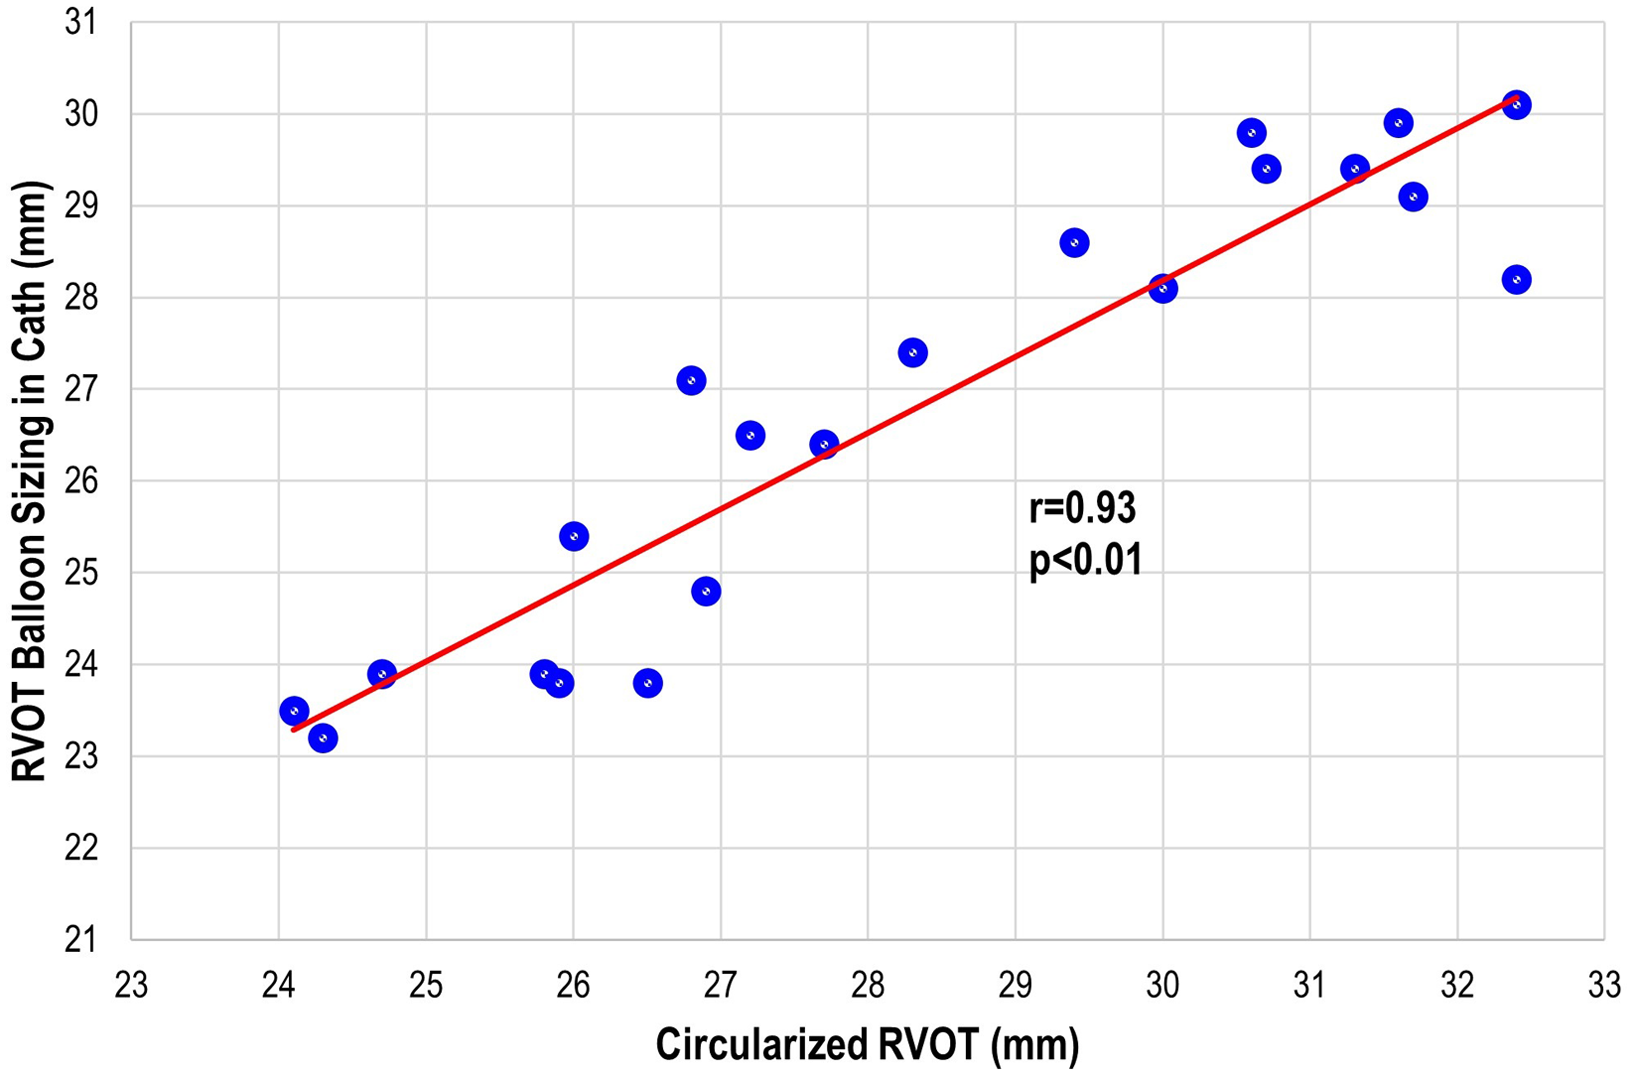

There were three patients (all within the transcatheter cohort) that did not have the non-contrast steady-state free-precession magnetic resonance angiography available, and the Twist sequence was utilised. The mean landing zone perimeter of the transcatheter cohort was 88.9 ± 8.7 mm and in the surgical/hybrid cohort measured 106.6 ± 7.5 mm (Fig 2). The two-dimensional diameter measurements from the same identified intended valve site within the transcatheter cohort were median 24.7 mm (range 19.9–27.2) in the smaller dimension and 31.3 mm (27–38.1) in the larger. For the surgical/hybrid cohort, this was 26.3 mm (22.5–33.1) and 39.7 mm (36.2–48.6), respectively. For the transcatheter cohort, the median “circularised” diameter derived from the MRI perimeter measurement (divided by π) was 27.7 mm (range 24.3–32.4). Notably, this correlated (r = 0.93, p < 0.01) with the median diameter of the narrowest region during actual transcatheter landing zone balloon sizing (lateral imaging) of 27.1 mm (range 23.2–30.1) (Fig 3). After transcatheter valve implantation, the mean outer diameter of the implanted prosthesis was 26.7 ± 2.2 mm. In comparison, the median circularised diameter based on the MRI-perimeter in the surgical/hybrid cohort was 33.5 mm (range 30.3–38).

Figure 3. Transcatheter pulmonary valve replacement cohort: correlation plot of the actual right ventricular outflow tract (RVOT) sizing during cardiac catheterisation to the circularised RVOT tract derived from the perimeter measurement on advanced imaging.

Various advanced imaging modalities have been explored in regards to guiding transcatheter valve replacement, including intravascular ultrasound. Reference Rudzinski, Kalinczuk, Mintz and Demkow22,Reference Kalinczuk, Mintz, Chmielak, Rudzinski and Witkowski23 Ebel et al compared invasive balloon sizing results with advanced imaging (cardiac magnetic resonance angiography) analyses and demonstrated the highest correlation coefficients for the maximum and effective diameter measured in systole. Reference Ebel, Gottschling and Buzan24 Curran et al calculated retrospective CT measurements of the right ventricular outflow tract in patients with landing zone dysfunction that underwent attempted transcatheter pulmonary valve replacement. Reference Curran, Agrawal and Kallianos15 This entailed landing zone circumference-derived and area-derived diameter parameters which correlated well with implanted valve size, especially in native right ventricular outflow tract or pulmonary bioprosthesis. A predicted valve category was generated for each patient using four diameters (maximum, minimum, area, and circumference), which was then compared to the category of the implanted transcatheter valve. Our study highlights consideration to a parameter able to be extracted from the standard workup for pulmonary valve replacement in most institutions (MRI) in addition to the standard diameter measurements in the orthogonal planes. The landing zone perimeter and the extrapolated circularised diameter was then compared to patient outcomes and candidacy for transcatheter pulmonary valve replacement that demonstrated correlation. This speaks to its potential clinical utility as well as reduction in measurement variability across users.